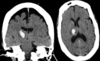

Du modtager en 63-årig herre, der er fundet i hjemmet af sin søn, efter man ikke har haft kontakt til ham i en dags tid. Han er kendt med hypertension men i øvrigt fuldstændig rask.

Ved neurologisk undersøgelse finder du ekspressiv og impressiv afasi, apraksi, højresidig central facialis parese samt nedsat kraft i højre overekstremitet. Efter aftale med radiologen foretages CT-scanning uden IVkontrast.

Hvad er den mest sandsynlige diagnose?

a. Intet abnormt.

b. Følger af venstresidigt infarkt, men intet der kan forklare det aktuelle sygdomsbillede

c. Subakut venstresidigt mediainfarkt

d. Traumatisk betinget ødem

e. Primær venstresidig hjernetumor med omkringliggende ødem

Du modtager en 63-årig herre, der er fundet i hjemmet af sin søn, efter man ikke har haft kontakt til ham i en dags tid. Han er kendt med hypertension men i øvrigt fuldstændig rask.

Ved neurologisk undersøgelse finder du ekspressiv og impressiv afasi, apraksi, højresidig central facialis parese samt nedsat kraft i højre overekstremitet. Efter aftale med radiologen foretages CT-scanning uden IVkontrast.

Hvad er den mest sandsynlige diagnose?

a. Intet abnormt.

b. Følger af venstresidigt infarkt, men intet der kan forklare det aktuelle sygdomsbillede

c. Subakut venstresidigt mediainfarkt

d. Traumatisk betinget ødem

e. Primær venstresidig hjernetumor med omkringliggende ødem